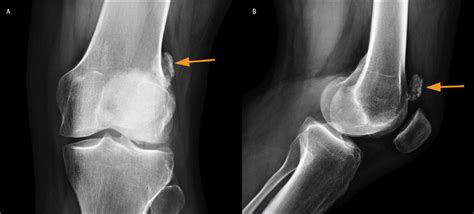

Patellar Sleeve Fracture The Western Journal of Emergency Medicine